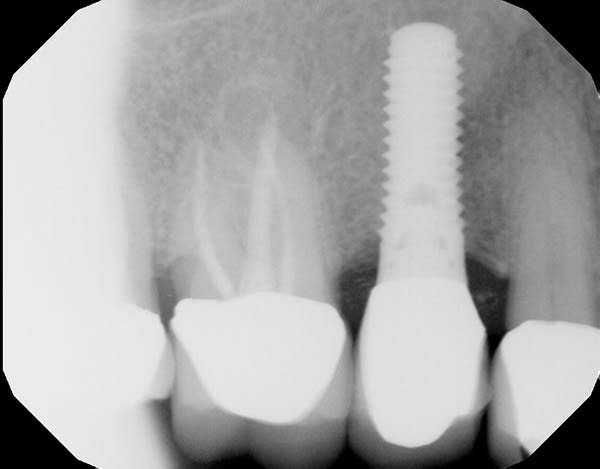

A 63-year-old male patient was referred in 2015 after a routine cleaning at his restorative dentist revealed pocketing and heavy bleeding on probing (BOP) around an implant in site No. 4. The implant (Straumann RN TE) had been placed in 2003 under the author's care due to a previous root fracture of the endodontically treated tooth No. 4, which had been extracted 6 months prior to presentation. The final implant crown was cemented with a polycarboxylate cement in 2003. The patient was highly compliant under his general dentist's care with regular 6-month prophylaxes. In 2015, the patient presented as a healthy non-smoker with a controlled medical history of atrial fibrillation and high cholesterol. Parafunctional habits were contributory to the failed tooth. The patient was diagnosed with site-specific beginning-to-moderate peri-implantitis around No. 4. LAPIP treatment using the PerioLase® MVP-7™ Nd:YAG laser (Millennium Dental Technologies, lanap.com) was performed. At 2 weeks' follow-up, the patient reported 0 out of 10 on a discomfort scale. He maintained good plaque control and returned to his restorative dentist's care after 6 months of healing for alternating periodontal maintenance visits every 3 months. At 7 years' postoperative, the peri-implant tissues associated with No. 4 were healthy with ≤4 mm probing depths and light BOP.